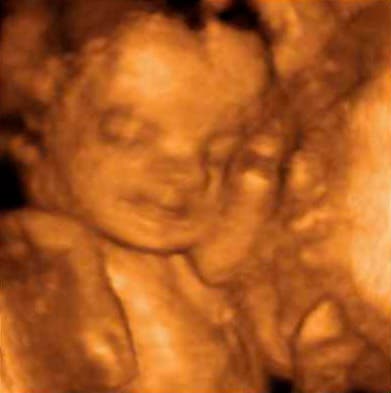

Беременность 7 месяцев: развитие плода

К 28-й неделе ребенок уже окончательно сформировался и уже может жить вне животика мамы. Его вес достигает 1,5 кг, а рост — 38-40 см, кожа приобретает розовый оттенок, а жировая ткань продолжает накапливаться.

Развитие плода:

- легочная система завершает формирование — малыш уже может делать первые дыхательные движения, но система вентиляции легких пока еще недостаточно развита;

- у плода полностью сформированы половые органы;

- малыш уже хорошо слышит и различает голоса;

- на его головке появляются первые волоски;

- головной мозг и нервные клетки активно функционирует, за счет чего кроха может ощущать боль;

- хорошо развит полный спектр чувств — осязание, обоняние, вкус и зрение;

- ребенок очень энергичен, а иногда даже гиперактивен.

К седьмому месяцу малыш занимает уже правильную позу перед родами, ложится головкой вниз. К 32-й неделе ему становится тесно в животике мамы и он начинает набираться сил перед родовым процессом, в связи с чем реже толкается.

Чаще всего повышенная активность или затишье ребенка в животике у мамы считается нормой, но гинеколог может назначить дополнительное УЗИ, чтобы убедиться в отсутствии гипоксии плода и задержки в его развитии.